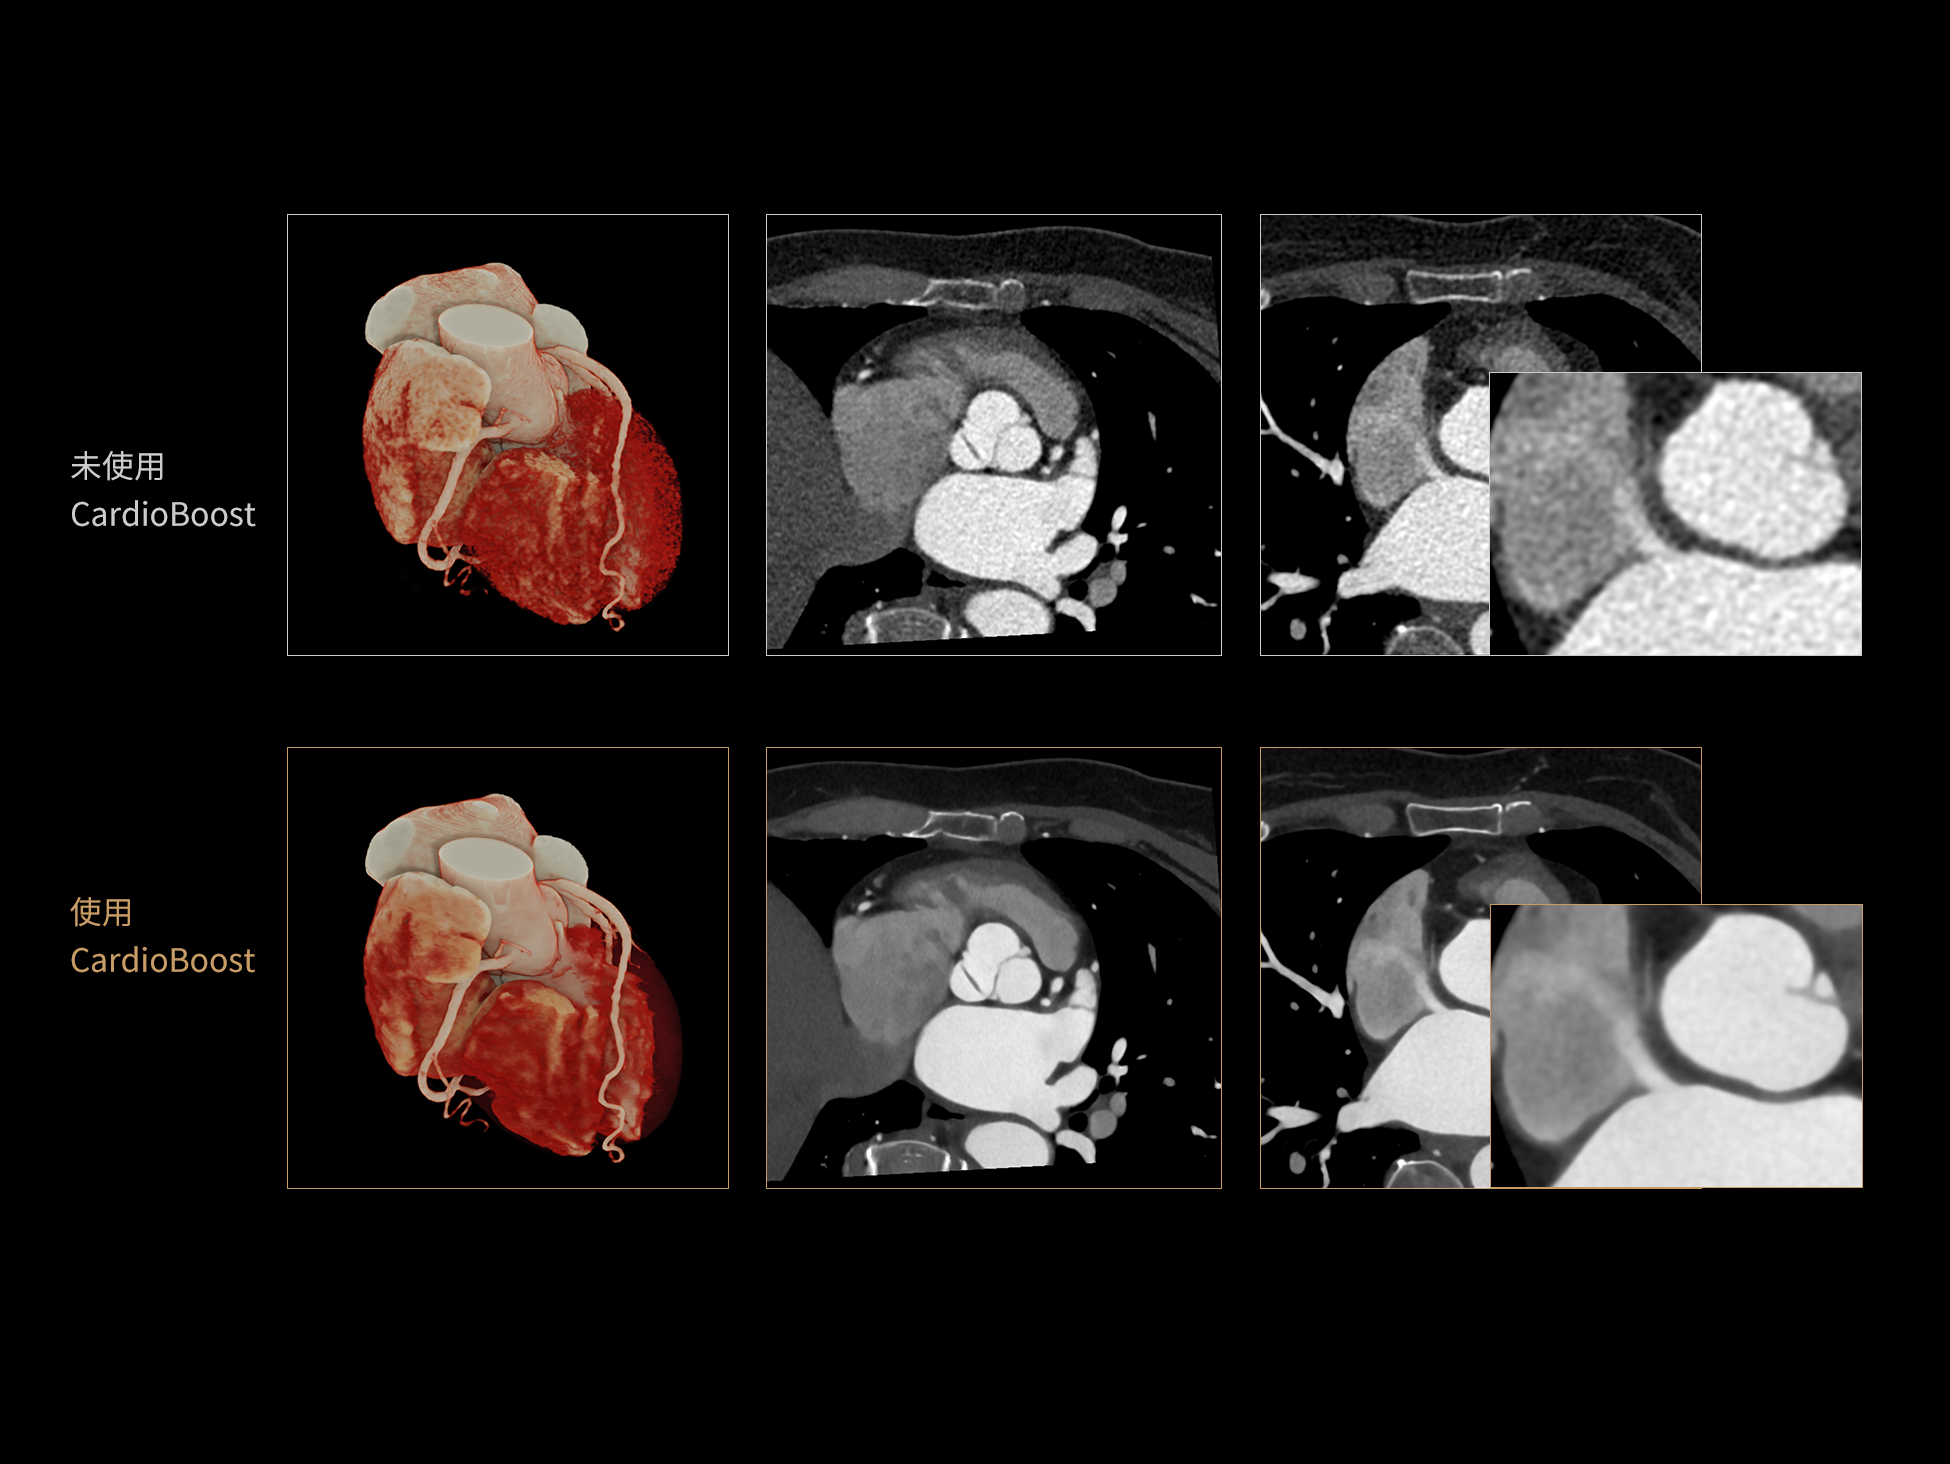

相同辐射剂量条件下

图像噪声减少